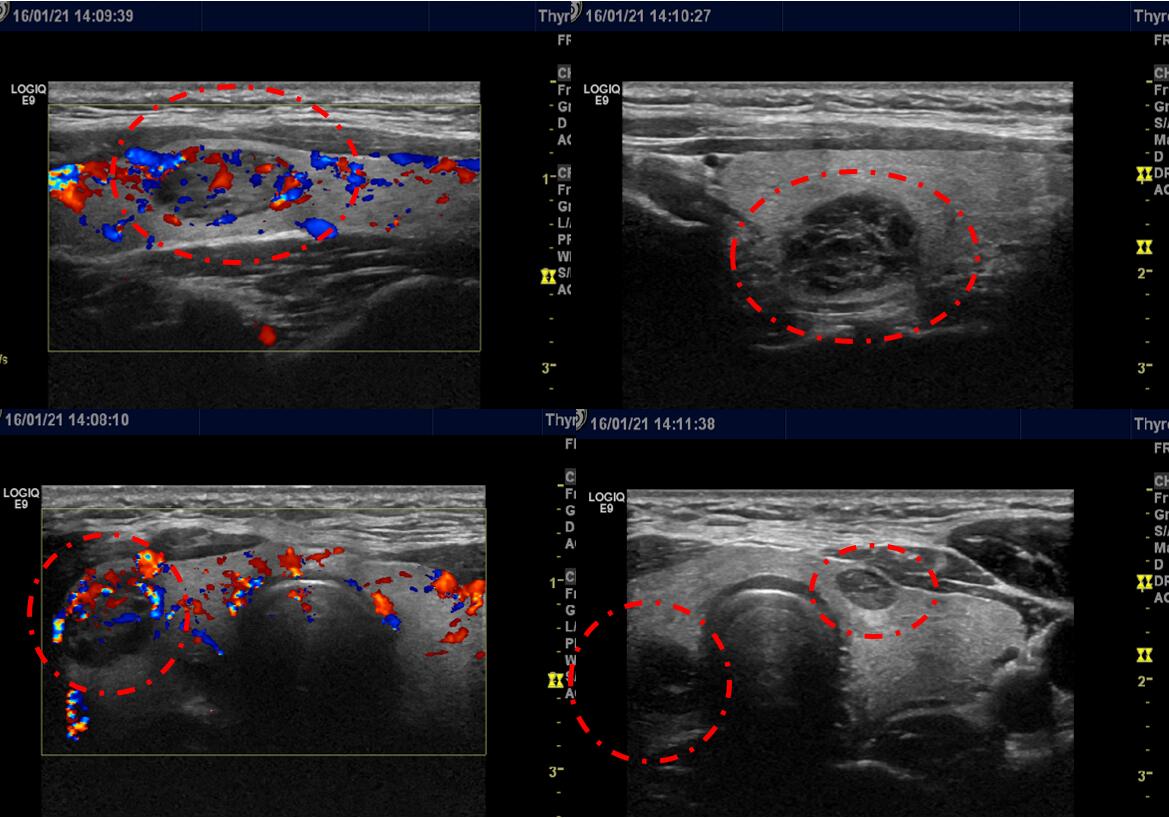

34岁的李女士2015年7月单位体检发现甲状腺双侧叶长了多个结节,最大的结节为23mm*15mm*13mm。李女士知道自己甲状腺长了多个结节则到当地医院就诊,医生认为李女士结节多个且较大结节超过两公分,需要治疗,因双侧也都有结节,手术切除范围大,术后很可能需要长期服用优甲乐,若不愿意开刀手术切除,则可以到广州行介入微创消融治疗,可以消灭结节的同时尽可能多的保留正常甲状腺组织。李女士观察且犹豫了半年,再次复查时甲状腺结节少许增大,部分囊性变,同时,李女士了解到广东省第二人民医院介入科是广东省较早开展甲状腺结节细针穿刺活检及甲状腺良性结节微创消融治疗的科室。李女士才下定决心到广州治疗,在广东省第二人民医院介入科就诊超声检查显示甲状腺双侧叶多发结节并结节部分囊性变(如下图)。#健康科普挑战赛#